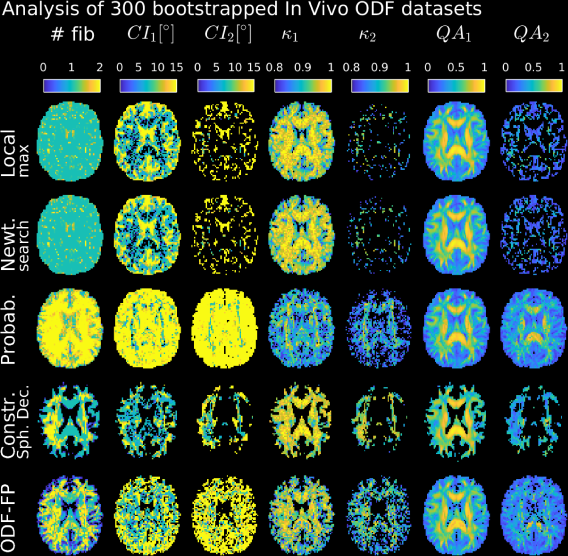

Refer to caption

Figure 9: Reproducibility and noise sensitivity analysis of fiber identification in 300 bootstrapped RDSI datasets. Fibers are identified by local maximum search (DSIStudio, top row), Newton search (MRtrix3, 2nd row), probabilistic estimation (FSL, bedpostx, 3rd row), constrained spherical deconvolution (MRtrix3, dwi2fod msmt_csd, 4th row), and ODF-Fingerprinting (ODF-FP, bottom row). Displayed are the number of fibers identified and 95% confidence intervals (CI), coherence (κ𝜅\kappa) and Quantitative Anisotropy (QA) values for the first and second fiber.

Analysis of 300 bootstrapped RDSI datasets (Fig. 9) shows that ODF-FP identifies crossing fibers where expected (Fig. 9, #fib-column on the left) while CSD finds them to a lesser extent, ODF maximum search methods miss fibers and probabilistic estimation identifies an artificially high number of fibers. In addition, CSD and ODF-FP do not identify as many fibers in areas where no fibers are expected such as the Cerebrospinal fluid (CSF). This leads to different patterns in the reproducibility and noise sensitivity statistics (95% confidence intervals (CI) and coherence κ𝜅\kappa, Fig. 9). QA-maps further illustrate these altered patterns (Fig. 9, QA𝑄𝐴QA-columns).

When fibers are identified with ODF-FP, the 95% CI and κ𝜅\kappa of the fibers are similar to the reproducibility values found for ODF maximum search methods and CSD, even for the second identified fiber (CI2𝐶subscript𝐼2CI_{2}, κ2subscript𝜅2\kappa_{2}-columns of Fig. 9). The 95% CI and κ𝜅\kappa maps further show the noise sensitivity of the probabilistic method with higher 95% CI and lower κ𝜅\kappa-values.